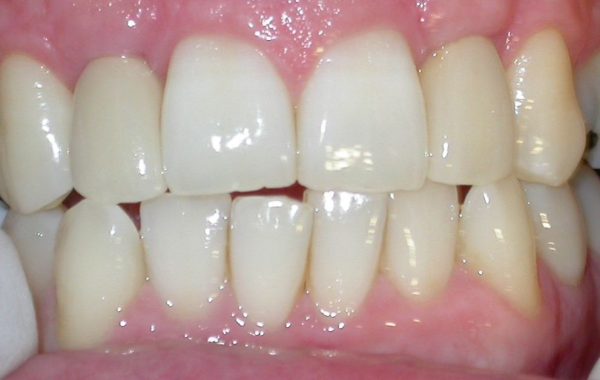

En el siguiente caso se muestran imágenes de una paciente de 35 años de edad, la cual perdió los dientes centrales y laterales del maxilar. La paciente quería una prótesis fija con alta estética. Le mostraremos a continuación la secuencia de este tratamiento.

Paciente que perdió dientes centrales y laterales superiores

Coronas finales colocadas sobre los Implantes Dentales

Foto final de la rehabilitación